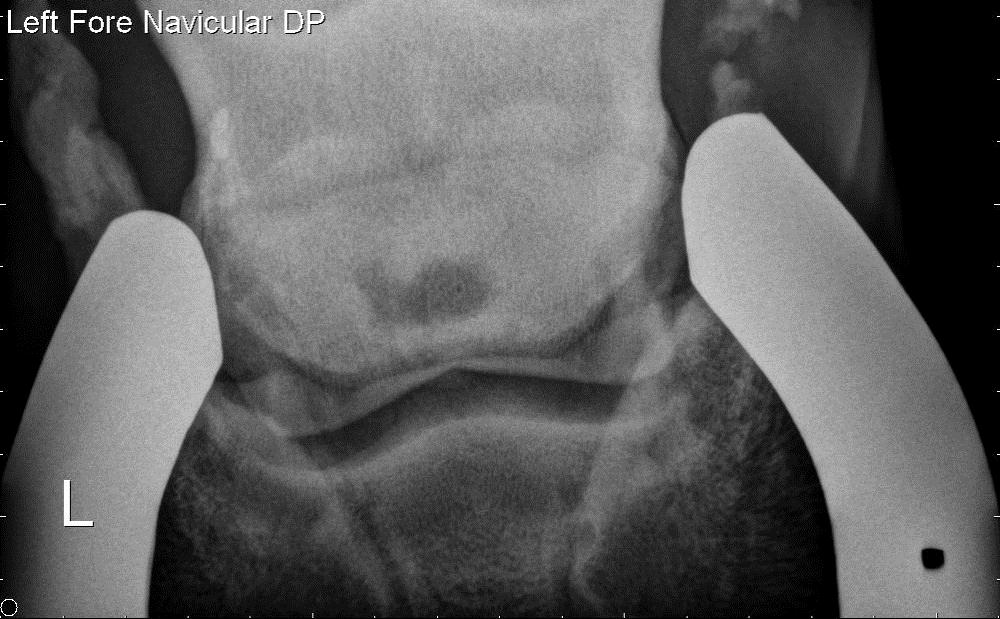

Horse Navicular X Ray . radiographs (x rays) are still important for examining the hoof’s bony structures and changes that are occurring. accurate radiographic evaluation of the navicular bone depends on a radiograph that is properly positioned and exposed and on a foot that is free of distracting artifacts. Many horses have pain in the heel region, which can be elicited by hoof testers. Radiographs will show any degenerative. However, researchers have found in. Abnormalities in the navicular bone navicular in horses relates to problems associated with the navicular bone in the horse’s hoof and is a common diagnosis for lameness in the front foot. Proper preparation for navicular radiography is similar to that for the distal phalanx, as discussed in chapter 23. a study looking at 72 horses that underwent mri for recent onset of navicular syndrome but without abnormalities detected on radiographs found the following: diagnostics involved in determining whether a horse has navicular syndrome include: Most horses show marked improvement in lameness with a palmar digital nerve block.